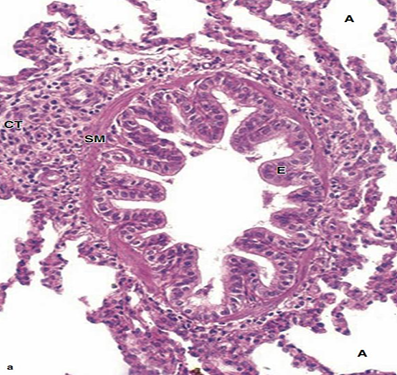

Section showing bronchiole and alveoli

Red = alveoli

Section showing bronchiole and alveoli (white spaces all around)

Red A = Artery

Bronchiole

Mucosa:

Epithelium: simple columnar to cuboidal partially ciliated with club cells

- Lamina propria: thin & contain elastic fibers.

Muscle layer: thin layer of circularly arranged smooth muscle.

- No goblet cells,

- No cartilage,

- No glands,

- No lymph follicles